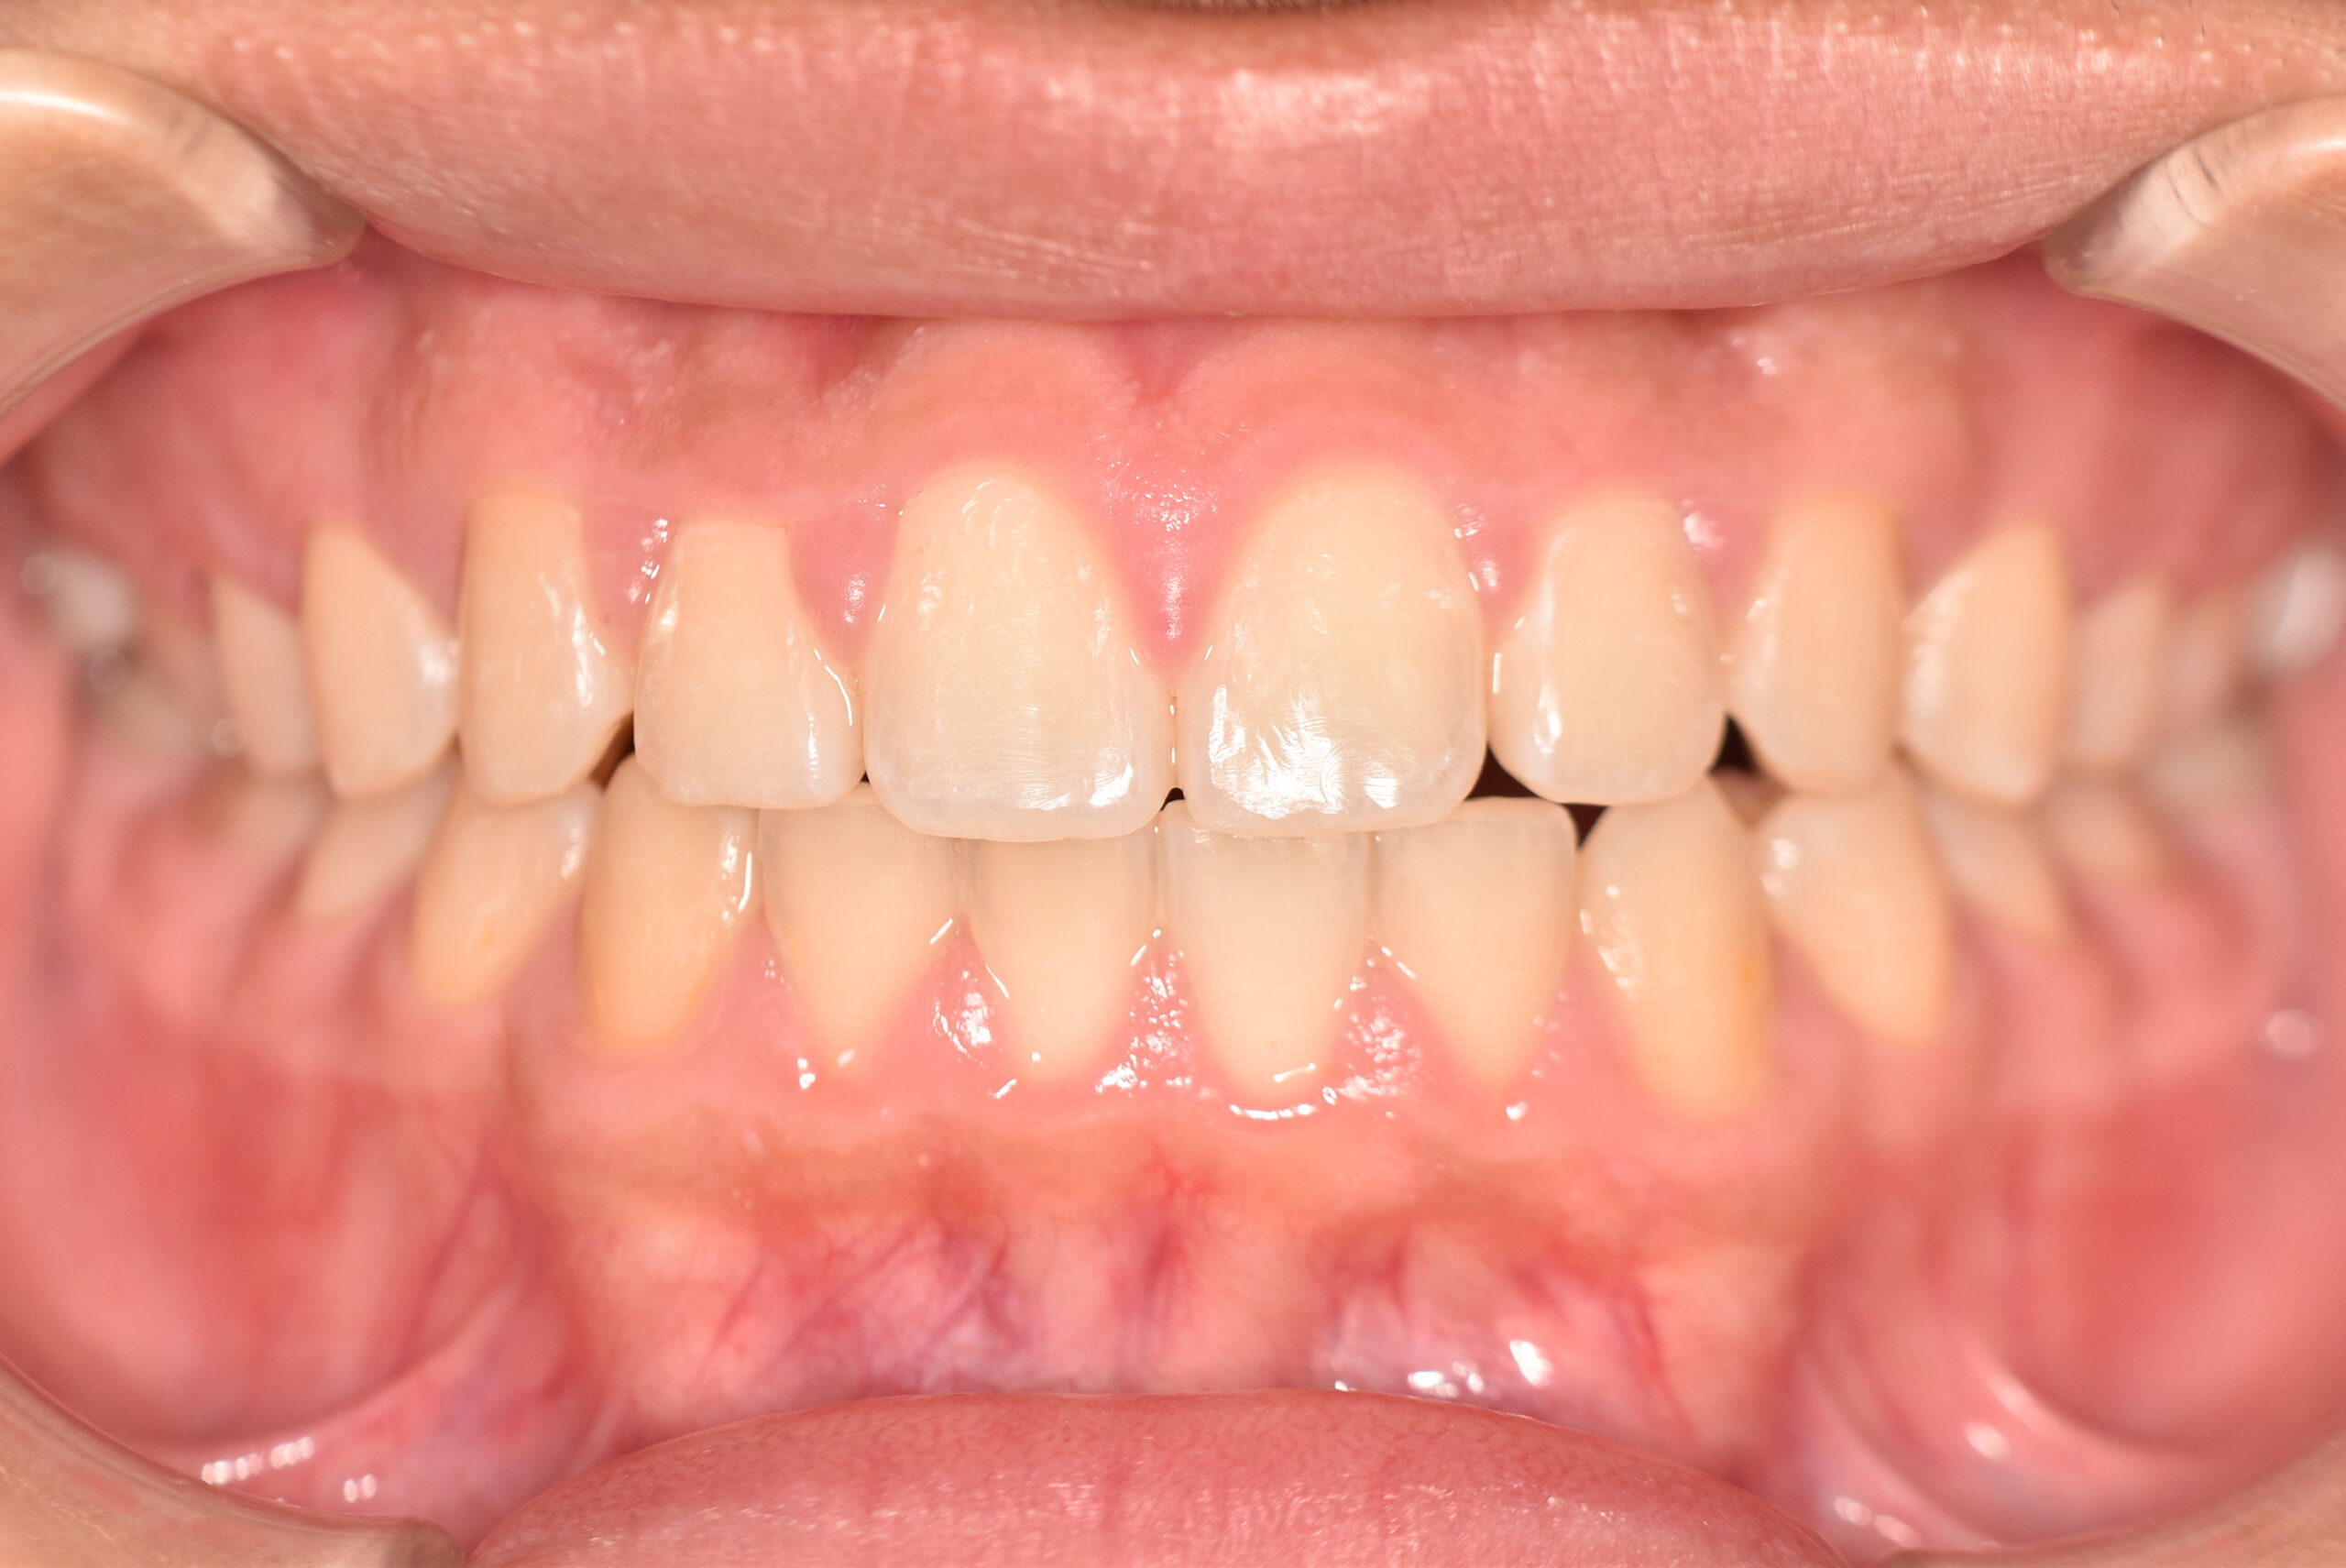

上顎前突(非抜歯)[2121]

動的治療終了時

症例 症例 症例 症例

治療内容の詳細 初診時8歳の男性で、癒合歯があり今後の歯並びが心配で来院されました。

検査の結果、過蓋咬合、上顎前突を伴うアングルⅡ級1類不正咬合と診断しました。

治療としては、初期段階の治療として、機能的矯正装置で鼻呼吸の獲得と舌の位置や口唇の閉鎖といった筋機能習癖の改善を行いました。

永久歯列に交換後、非抜歯の上、セルフライゲーションブラケット装置(デーモンシステム)で歯の配列と咬合関係の改善を行いました。

治療期間は、5年10ヶ月でした。